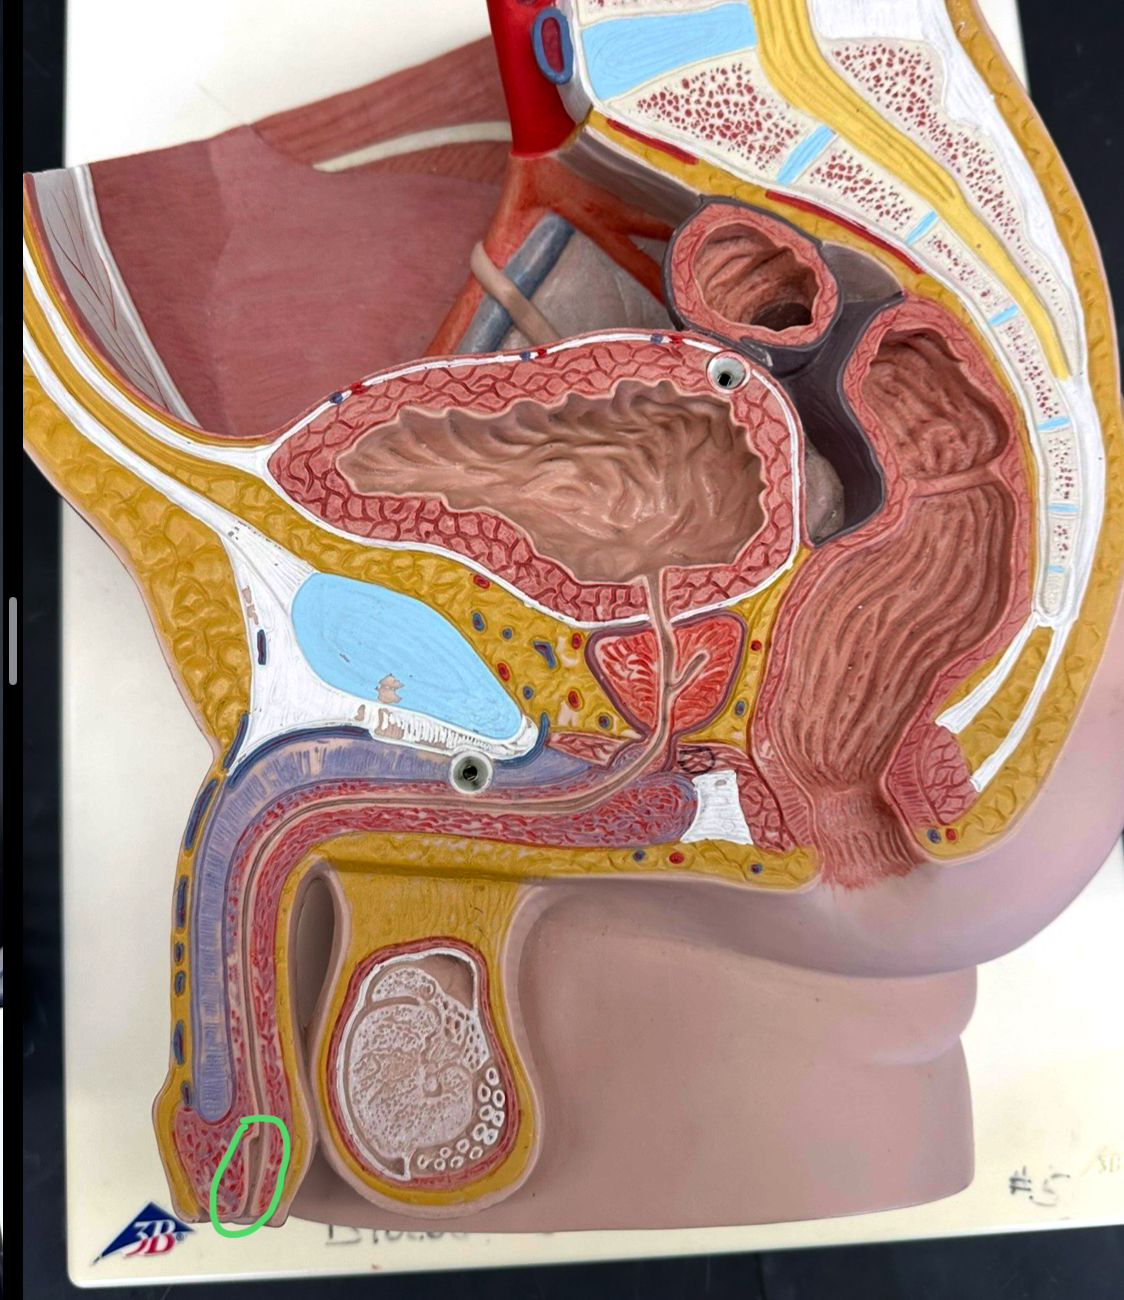

bulbourethral gland

whole